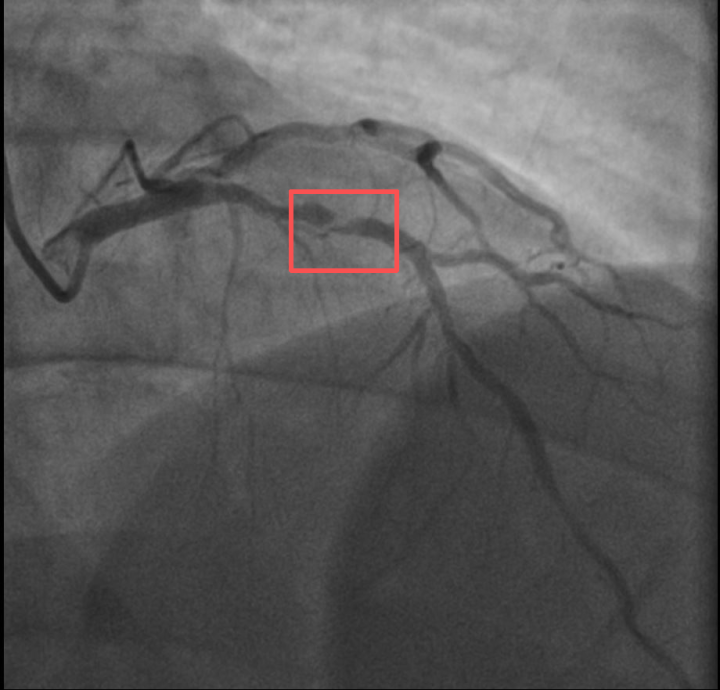

Core Viewpoint - The article highlights a critical case where a patient initially misdiagnosed with gastrointestinal issues was actually suffering from an acute myocardial infarction, emphasizing the importance of thorough medical evaluation and timely intervention [2][4]. Group 1: Patient Case Summary - The patient, referred to as Mr. Xing, experienced sudden abdominal pain and initially believed it to be a common gastrointestinal issue [2][3]. - Despite a normal electrocardiogram, the attending physician, Dr. Yang, suspected a potential acute myocardial infarction and recommended further testing, which confirmed elevated cardiac troponin levels indicative of a serious heart condition [3][4]. - The patient was initially resistant to hospitalization and treatment, wanting to return home, but was eventually persuaded by the medical team to stay for necessary care [4][5]. Group 2: Medical Intervention - The patient was diagnosed with acute non-ST elevation myocardial infarction after a rapid online consultation with the hospital's cardiology team [4][5]. - Upon arrival at the chest pain center, it was revealed that the patient had severe blockages in three coronary arteries, posing a significant risk of cardiac arrest [5][6]. - The medical team successfully performed a procedure to open the blocked arteries, restoring blood flow and saving the patient's life [6]. Group 3: Medical Insights - The article underscores that symptoms of heart attacks can be atypical, such as abdominal pain, which can lead to misdiagnosis as gastrointestinal issues [8]. - It stresses the need for healthcare professionals to develop the ability to recognize disguised symptoms of serious conditions and to maintain persistence and sincerity in patient care [8].

Core Insights - Two 38-year-old fathers experienced acute myocardial infarction after engaging in vigorous physical activities, raising concerns about the risks associated with sudden intense exercise [1][5][12] Group 1: Case Studies - Mr. Sun, a badminton coach, suffered a heart attack after playing for about 10 minutes, despite having lost weight and previously being diagnosed with significant coronary artery issues [3][5] - Mr. Qian experienced chest pain the day after hiking with his child, leading to a diagnosis of myocardial infarction, exacerbated by his poorly controlled high blood sugar levels [5][7] Group 2: Medical Analysis - Doctors indicated that vigorous exercise can trigger heart attacks through mechanisms such as plaque rupture, oxygen supply-demand imbalance, and vascular spasm [9][10] - The presence of unstable atherosclerotic plaques in coronary arteries can lead to severe complications during intense physical exertion [9][12] Group 3: Recommendations for Prevention - Individuals with potential heart issues should undergo cardiovascular risk screening and assess their heart's tolerance to exercise before engaging in high-intensity workouts [12][13] - A gradual approach to increasing exercise intensity, proper warm-up and cool-down routines, and avoiding extreme conditions are essential for safe physical activity [13][14]